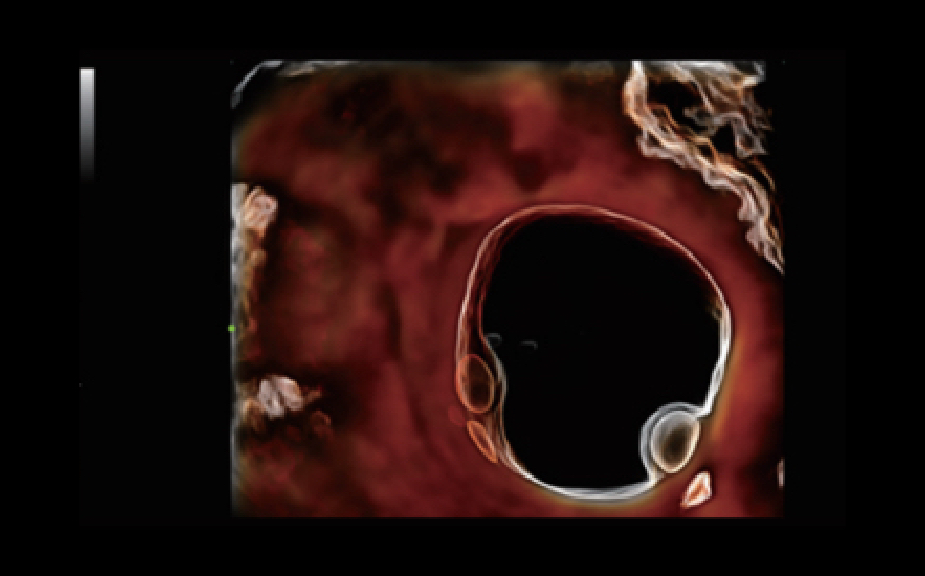

Platform ZST+ merupakan inovasi luar biasa yang mewakili evolusi ultrasound. Mentransformasikan metrik ultrasound dari pembentukan cahaya konvensional menjadi pemrosesan berbasis channel data. Mengatasi batasan kompromi tradisional antara resolusi spasial, resolusi temporal, dan keseragaman jaringan, menghadirkan mutu gambar yang luar biasa untuk solusi pencitraan tak terbatas dengan peningkatan secara berkelanjutan.

Gambar Klinis